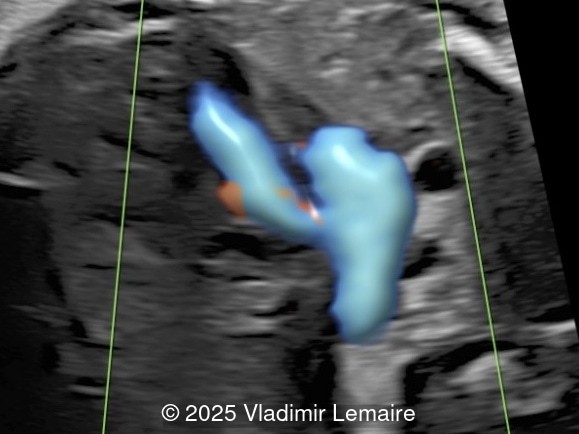

STIC of the three-vessel-trachea view with color Doppler coupled with volume contrast imaging (VCI-A).

Image 4 STIC of the three-vessel-trachea view with color Doppler coupled with volume contrast imaging (VCI-A).